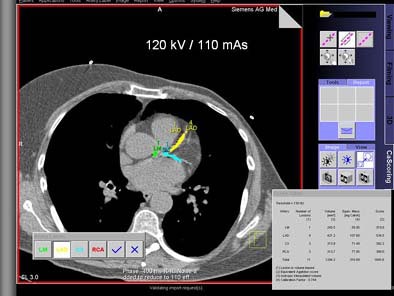

"Since you can’t scan those patients multiple times, we used a software platform to add artificial image noise," Schoepf said. The Vamp syngo Explorer application was applied to the resulting images to simulate reduced mAs of 150, 130, 110, 90, 70, and 50 in consistent regions of interest over the left ventricle. All three methods of calcium scoring were again applied in the usual manner at all noise degradation levels. Scoring variations at low-dose settings were again compared to those at the full dose, he said.

| Top, patient was scanned with 120 kVp/170 mAs. Below, artificial image noise was added using the Siemens Vamp syngo Explorer to simulate acquisition with lower dose settings at 120 kV/110mAs and 120kV/50 mAs. Calcifications in the left main coronary artery are highlighted in green, those in the left anterior descending coronary artery in yellow, and those in the left circumflex coronary artery in blue. The calcium scores at the three dose settings are not significantly different. Images courtesy of Dr. Joseph Schoepf. |